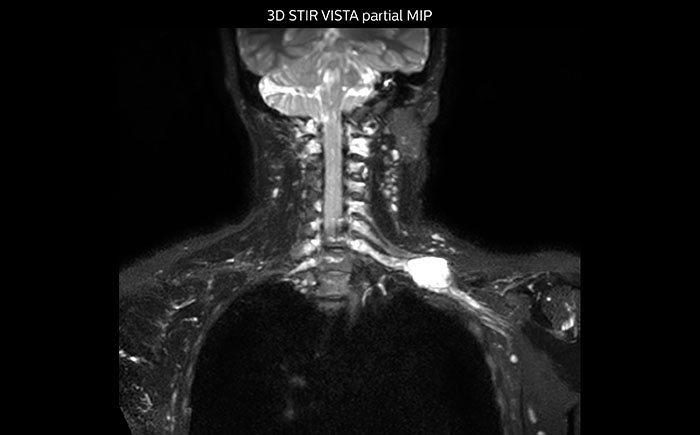

MR neurography of nerve sheath lesion

This patient is a 43-year-old female with a left supraclavicular nerve sheath tumor. The lesion is well visualized on the STIR VISTA images and on the MR neurography using DWIBS. The exam was performed on Prodiva 1.5T.

Whole body diffusion

MR neurography using DWIBS inverted, full MIP

Acq voxel size 1.2 x 1.3 x 2.4 mm, Recon voxel size 0.7 x 0.7 x 1.2 mm, dS SENSE factor 2, scan time 5:46 min.